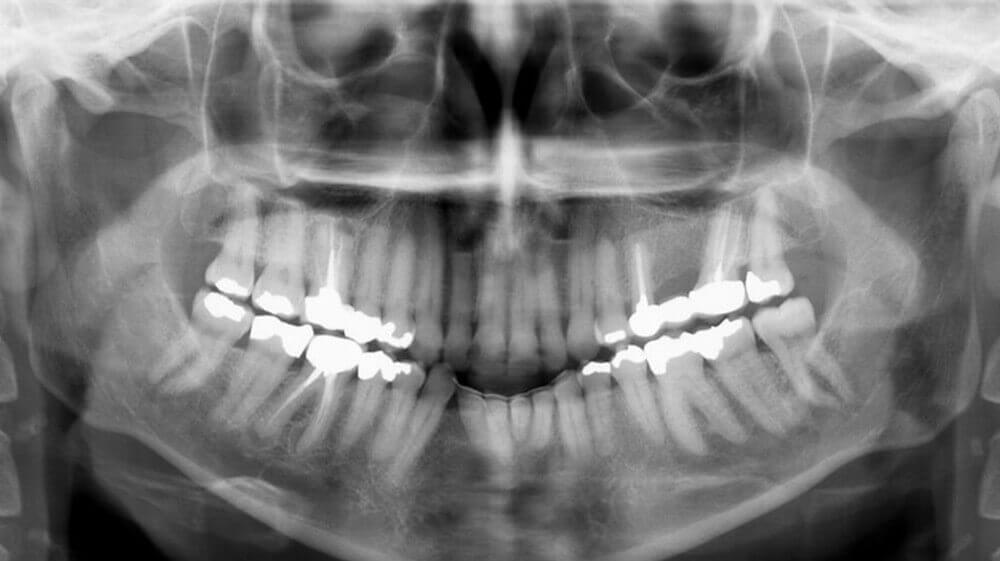

X-ray for aligner treatment

Usually, we have to first examine X-rays, since patients may have gone through RCT (Root Canal Therapy), and have implant crowns. By checking X-rays, we learn everything clearly and can make right planning for the whole treatment. You can easily have X-rays done in dental clinics or in hospitals. In many cases, however, you may have to first deal with your decayed teeth or even have certain teeth extracted. And you do not know when is the right time to treat with clear aligners.